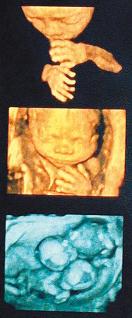

坊間相當流行拍攝「胎兒寫真集」,婦產科醫學會八日直斥,以三D、四D的立體超音波,讓準爸媽知道胎兒的長相,純粹就是「噱頭」,而且很好賺,因為每次自費至少二千至三千六百元,卻對產檢沒有任何幫助,孕婦根本沒必要額外花錢做這項檢查。

台灣婦產科醫學會昨天召開記者會,台大醫院產科病房主任徐明洸指出,台灣少子化,每個孩子都是父母的寶貝,近年不少婦產科醫療院所大力宣傳三D、四D立體超音波,號稱可搶先看到胎兒長相,但婦產科醫學會並不建議產婦接受立體超音波,他甚至認為,立體超音波完全只是商業噱頭。

徐明洸表示,並不是越多「D」的超音波就越好,一般來說,二D超音波是平面影像,三D呈現的是立體圖像,四D就是模擬成動畫影片,其實只要二D超音波,就能篩檢出六至八成構造異常的胎兒,三D超音波唯一的優點,就是滿足父母搶先看到寶寶的長相、生殖器官,娛樂效果大於實質。